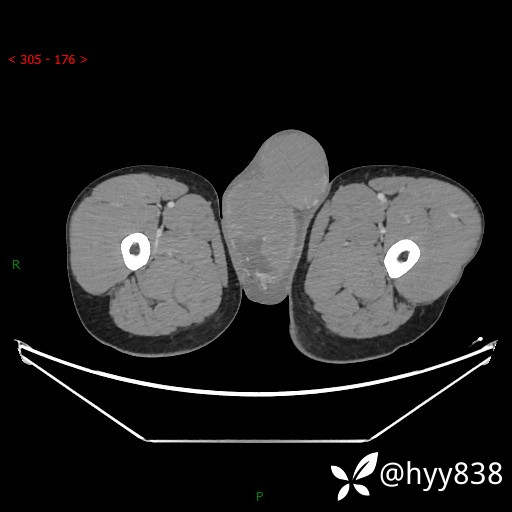

增强动脉期